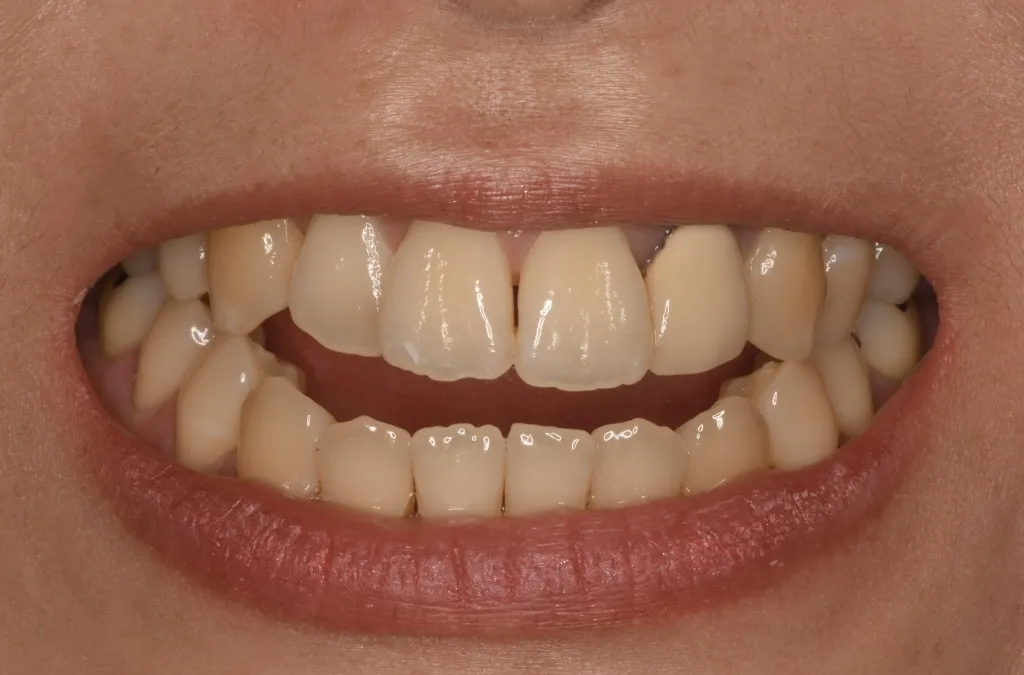

• 笑った時の状態 常に前歯が開いている

笑った時の状態 常に前歯が開いている

患者さんのお悩み、希望 前歯がまったく噛んでいないため、滑舌が悪く、前歯でものが噛み切れないことに悩まれていました。何件か矯正相談に行ったが、どこでも「顎を切る手術をしないと治らない」と言われ諦めかけていました。手術は回避したいが、噛み合わせを治したいという強いご希望がありご来院されました。

治療方法 マウスピース矯正(インプラントアンカー併用)。 開咬に加え受け口傾向であったため、ワイヤー矯正では手術が必要な歯並びでしたが、マウスピース矯正で奥歯を圧下し、インプラントアンカーを併用して下顎の奥歯を後方に移動させ、開咬と受け口を改善しました。